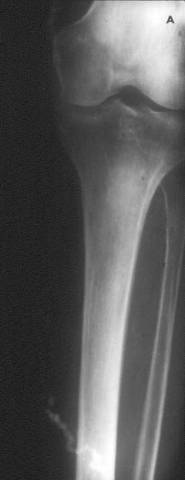

Calcified Venous Thrombus